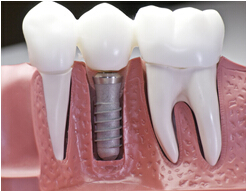

牙齿松动拖延治疗的情况在临床时有发生。许多患者都会拖到牙齿不能再治疗的时候才来医院就诊。而此时,牙齿直接接受拔除再镶的命运。然而对着医疗技术的不断发展,种植牙技术可以帮助我们完美解决松动牙脱落的问题。

淮安市口腔医院率先引进国际先进的即刻种植牙系统,拔牙的同时还可立即种植牙,完全不影响您的生活质量。种植完的牙齿,不但外观上和我们的真牙极其相似,更是恢复了我们真牙90%以上使用功能,咀嚼能力比传统镶牙方式大大提升。被誉为“人类除乳牙,恒牙外的第三幅牙齿”。